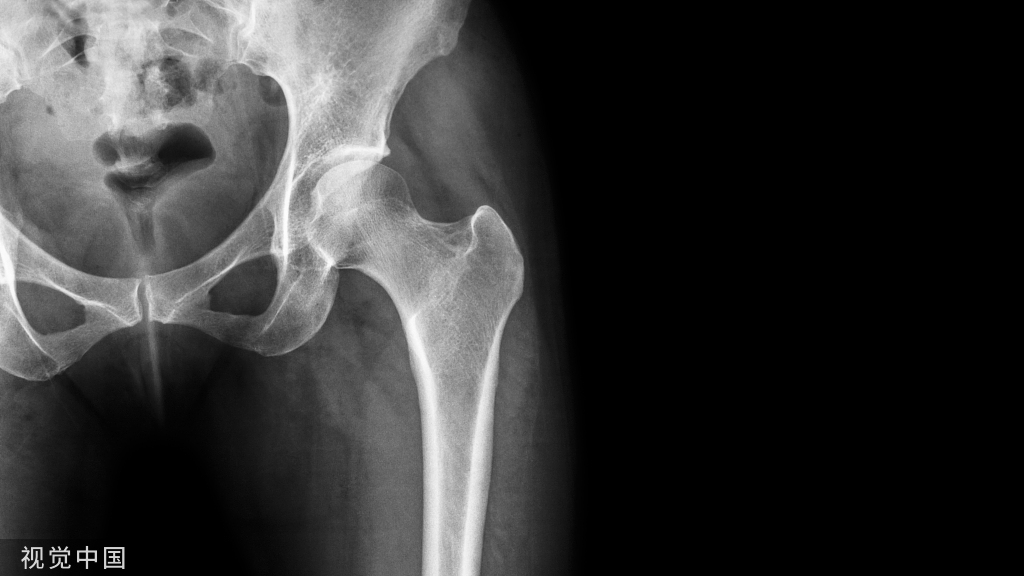

创伤或疾病造成大面积骨缺损的修复是一项重大临床挑战。金属材料具有良好机械性能、生物相容性和制造工艺,可用于骨缺损的修复。不锈钢和钛合金等传统金属材料已广泛应用于临床。可生物降解的金属材料,如铁、镁和锌合金,因其可随时间降解而成为骨修复的理想候选材料。新兴金属材料,如多孔钽和铋合金,因其对骨具有亲和性和多功能性,可作为骨植入物而备受关注。然而,这些金属材料仍有许多实际困难,亟待改进。

本文系统回顾和分析了用于骨修复的金属材料,全面概述了它们的形态、机械性能、生物相容性和体内植入情况。此外,本文还总结了解决金属材料不足的相关策略。最后,讨论了金属材料的发展前景,指导未来研究和临床实践的进步。